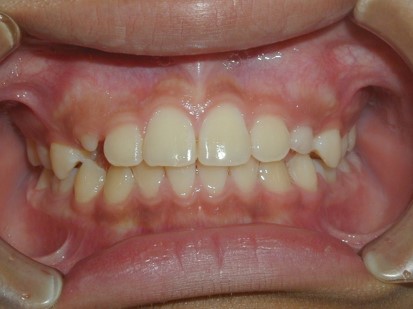

永久歯に交換するためのスペース不足による前歯のガタガタで、取り外しができる拡大床にて上下顎の幅を拡大した後、上顎の前歯をマルチブラケット装置で並べました。治療の期間は1年9か月でした。

終了時